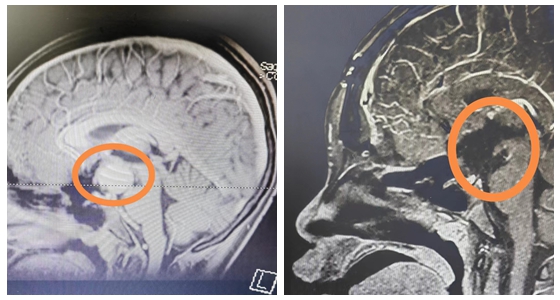

13岁的涵涵身高仅有145cm,体重37kg,比同班的男孩,甚至女孩都要矮小。起初,爸爸妈妈也没有太在意,以为孩子就是“长得晚”。2023年5月份开始,涵涵偶尔会跟爸爸妈妈说自己视物模糊,看不清,这时父母才重视,带涵涵到当地医院就诊。在医生的建议下查了颅脑MRI,问题果然出现在脑袋上,考虑:颅咽管瘤。为寻求手术治疗,涵涵在家长陪同下慕名来到湘雅常德医院神经外科就诊。

入院后,涵涵完善了相关辅助检查,经过袁贤瑞教授团队讨论分析后,为其制定了最适合的手术方式。术前告知家属术中、术后的风险且征得其同意签字确认后,袁贤瑞教授带领神经外科团队在显微镜下行鞍区占位切除术,术中肿瘤全切,手术顺利完成!